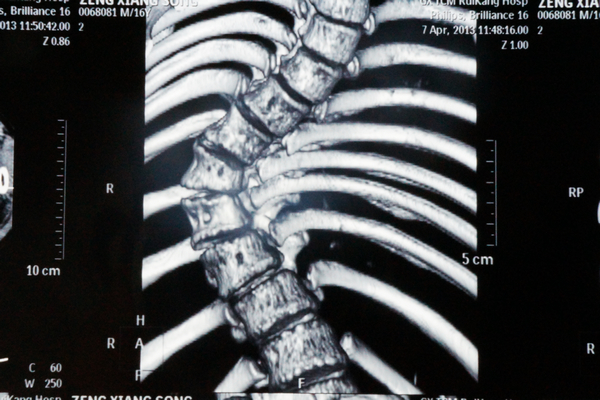

我院骨脊柱二区的医生给小松做了详细的身体检查,发现他的胸5-腰1椎体节段明显向右侧侧弯,呈小“S”形状,胸5-腰1棘突及棘突两旁无明显压痛及叩击痛,右侧竖脊肌肌张力紧张,左侧正常,站立姿势时测量左侧肩比右侧肩高约2cm。同时进行并足前屈弯腰试验时,发现小松的右侧肩胛骨明显高于左侧,出现“剃刀背”畸形,脊柱左右侧弯柔软性差,Cobb角65° ,胸腰椎MRI平扫检查确诊:脊椎侧弯畸形。

小松术前的X光片1